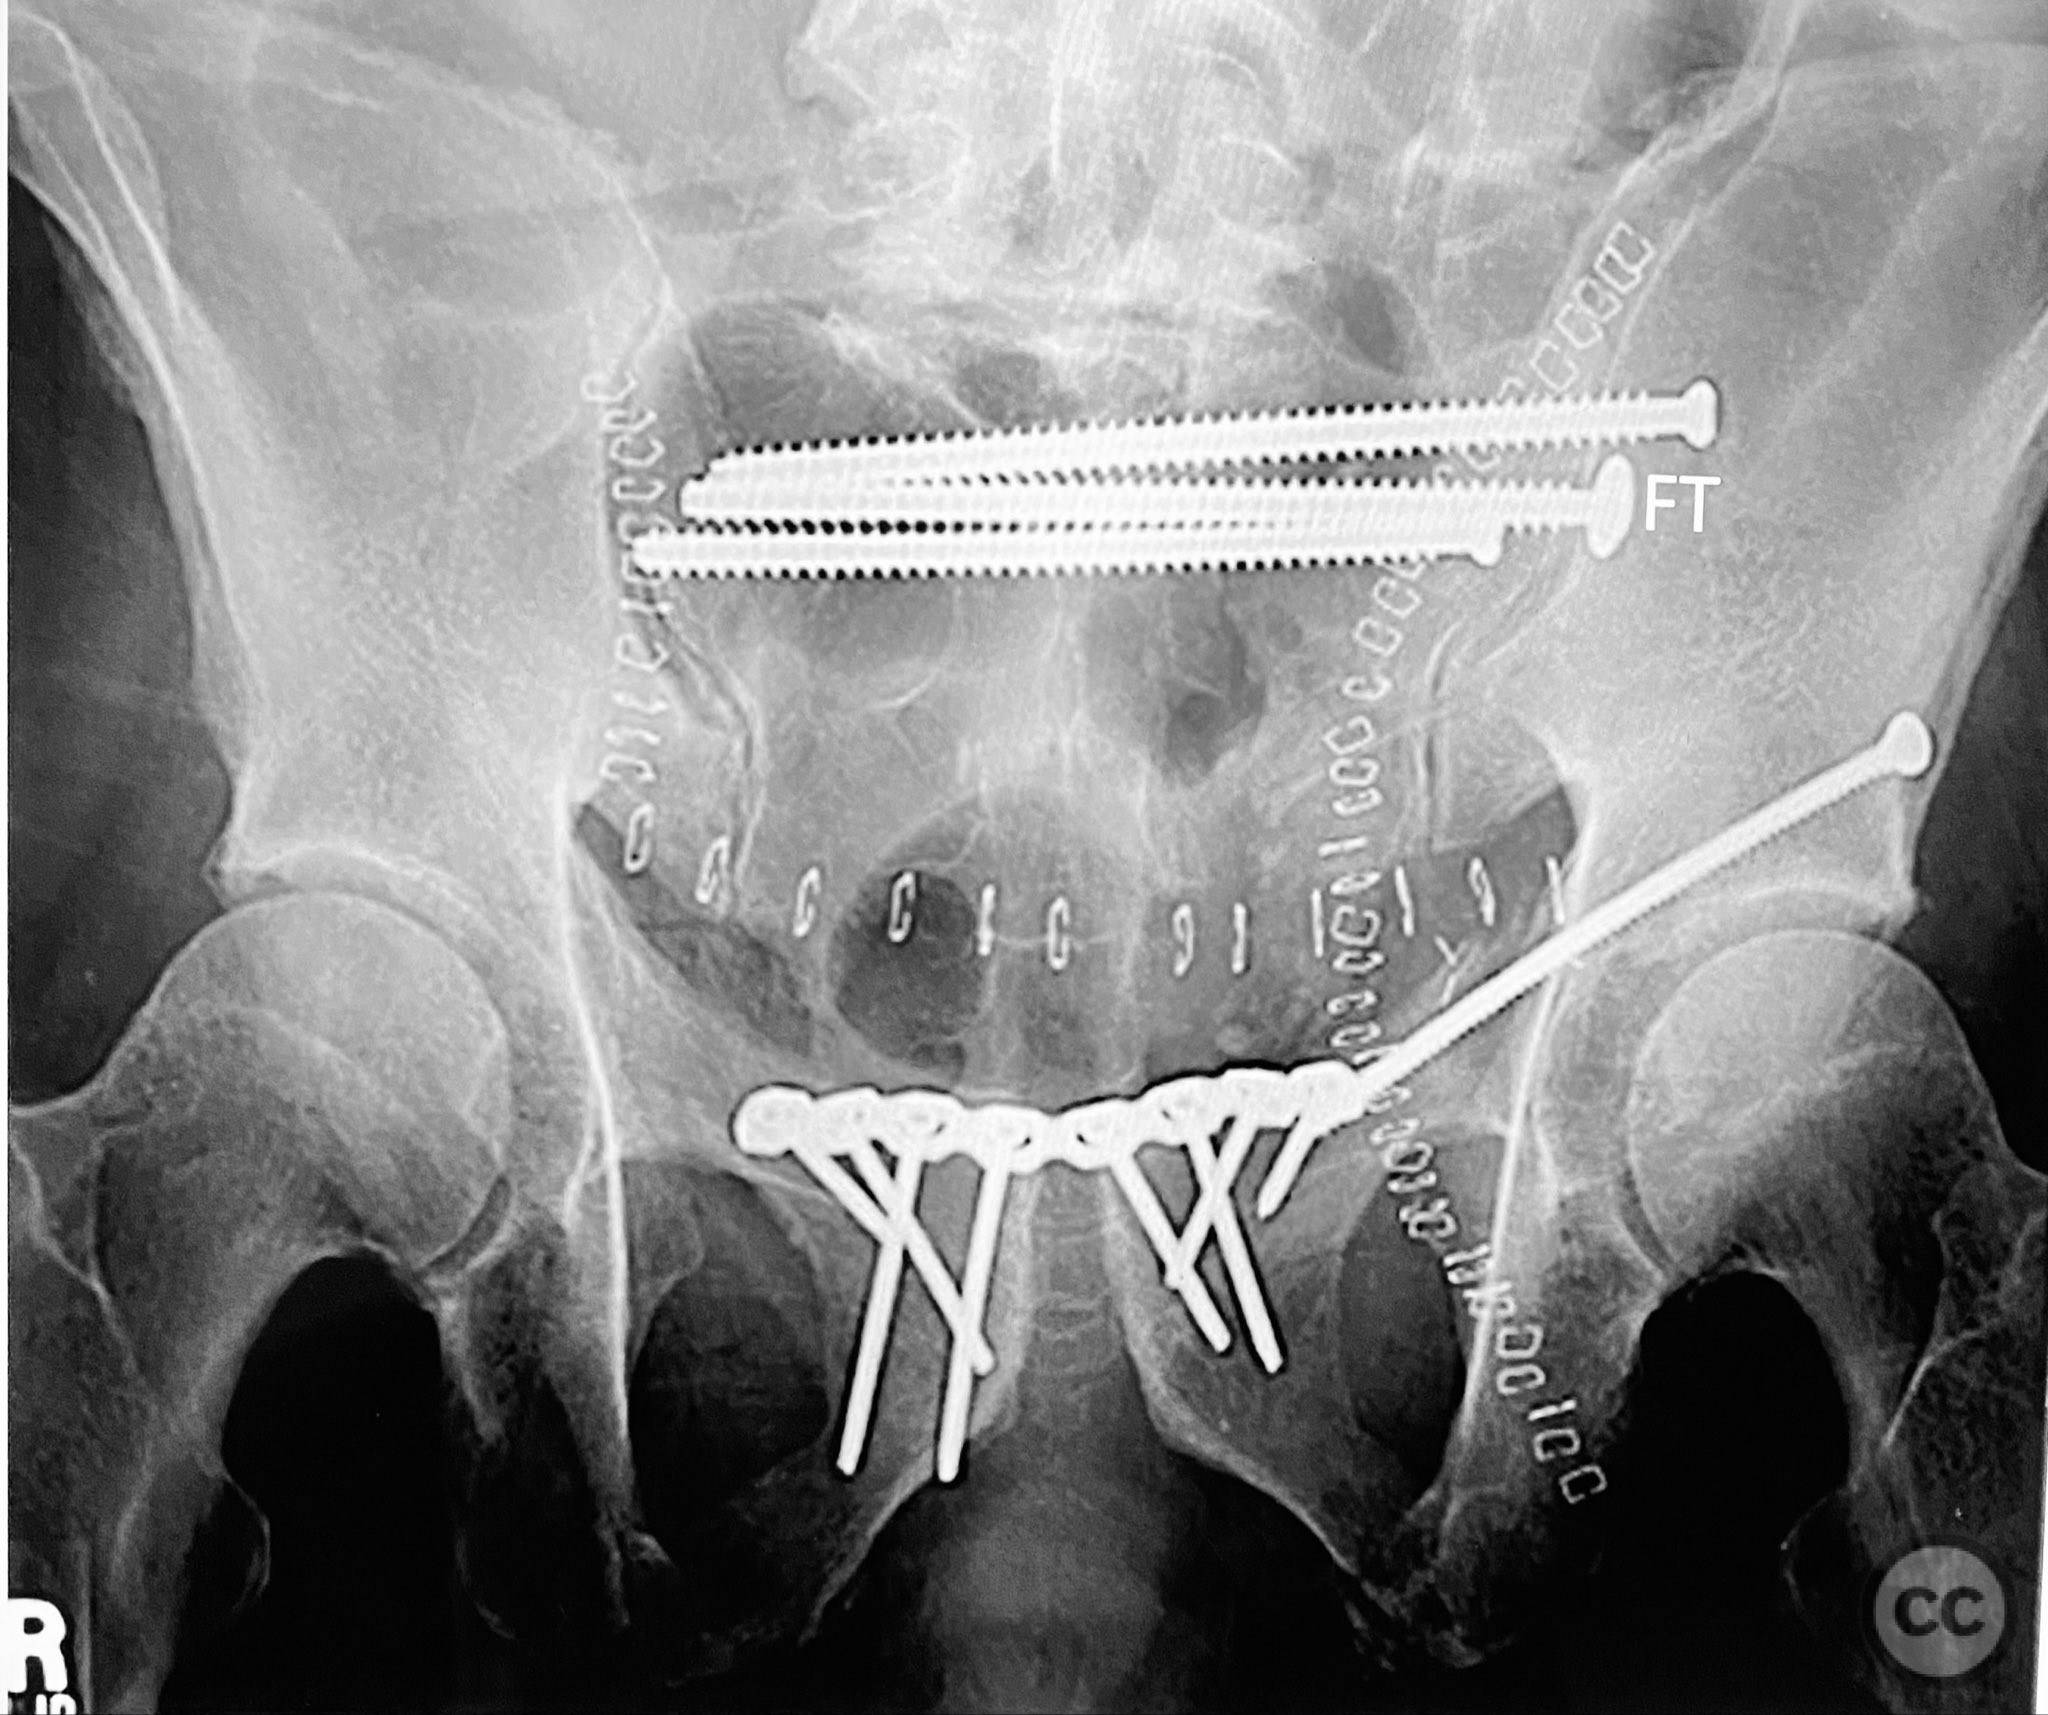

Anatomical surgical approach:  The posterior approach involved a midline longitudinal incision over the sacrum, subperiosteal dissection to expose the dorsal sacral cortex, and direct assessment of fracture reduction using the cortical edges as reference points. Reduction was achieved and maintained with clamps. Iliosacral screws were inserted percutaneously under fluoroscopic guidance, supplemented by a posterior transiliac screw traversing from one ilium to the contralateral ilium across S1/S2. The anterior approach utilized a Pfannenstiel incision for exposure of the symphysis pubis and adjacent rami; reduction was achieved with pointed reduction forceps and stabilized with a symphyseal plate and additional ramus screws as indicated.

The posterior reduction was facilitated by direct visualization of the dorsal sacral cortex, allowing precise assessment and clamping of the comminuted fragments prior to screw fixation. The iliosacral screws were placed without cannulated instrumentation longer than 130mm, reflecting historical implant limitations at the time of surgery. Postoperative CT confirmed satisfactory reduction and fixation of the posterior ring, though suboptimal positioning of iliosacral screws was noted (contained within the osseous fixation pathway but not optimized for maximal safety or precision). The anterior ring was subsequently addressed in a staged fashion, with anatomical reduction and stable fixation achieved via open technique. This case highlights technical challenges in achieving optimal screw trajectory and length, particularly with historical implant constraints, as well as the importance of staged management in complex pelvic ring disruptions.

Orthopaedic implants used:   7.3mm iliosacral screws (non-cannulated), posterior transiliac screw, anterior symphyseal plate, cortical screws for ramus fixation